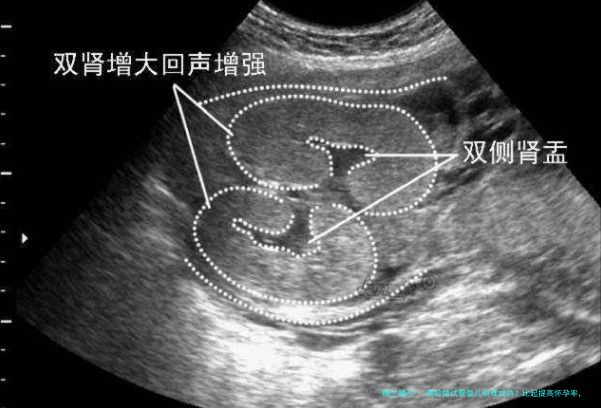

准时进行全方位的身体检查,尤其是针对生殖系统和激素水平的检测,可以帮助医生即时察觉问题并整合治疗方法。比如,通过超声波检查评介卵巢储存功能,血液尝试监测激素水平变迁等。